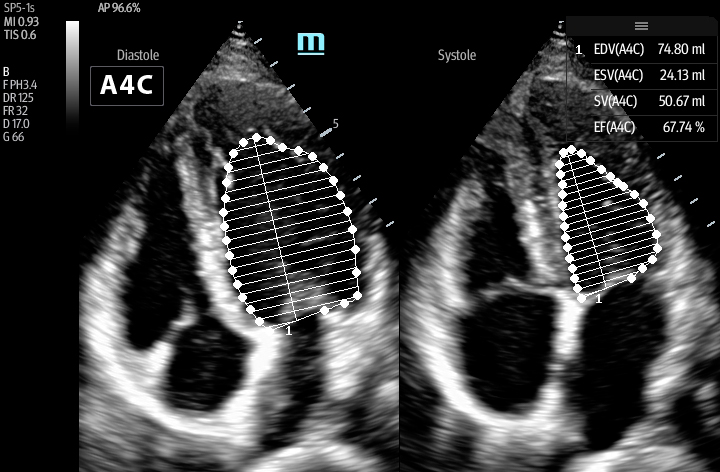

Smart VTI

Automated measurement of the Velocity Time Integral (VTI) and Cardiac Output (CO), enables rapid assessment of cardiac function. This software automatically locates color box and Pulse Wave Doppler (PW) sample line in real time. A graph of parameter trends for CO, Stroke Volume (SV) and VTI is produced to guide decision-making.